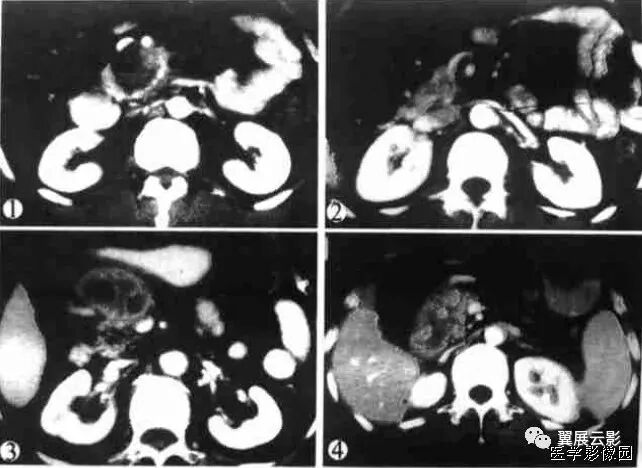

(该图来自《CT泪滴状肠系膜上静脉征评价胰头癌不可切除性的意义》一文, 中国医学影像技术2001年第17卷第2期)

图1 动态增强CT 示胰头部肿块紧邻 SMV、SMA,周围正常脂肪间隙消失,SMV受压呈泪滴状。

图2 螺旋增强CT 示胰钩突部一低密度肿块,SMA包绕受侵,SMV受压呈线形改变

图3 动态增强CT 示胰头部一密度不均匀肿块,与 SMV脂肪间隙消失,SMV受压呈椭圆形改变。

图4 螺旋增强CT 示胰头部一密度不均匀肿块,与 SMV脂肪间隙模糊但仍存在,三角形的 SMV为容积效应所致。